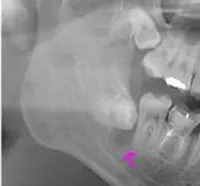

親知らず症例

手前に傾き、ひとつ前の歯の下に潜っている親知らず。